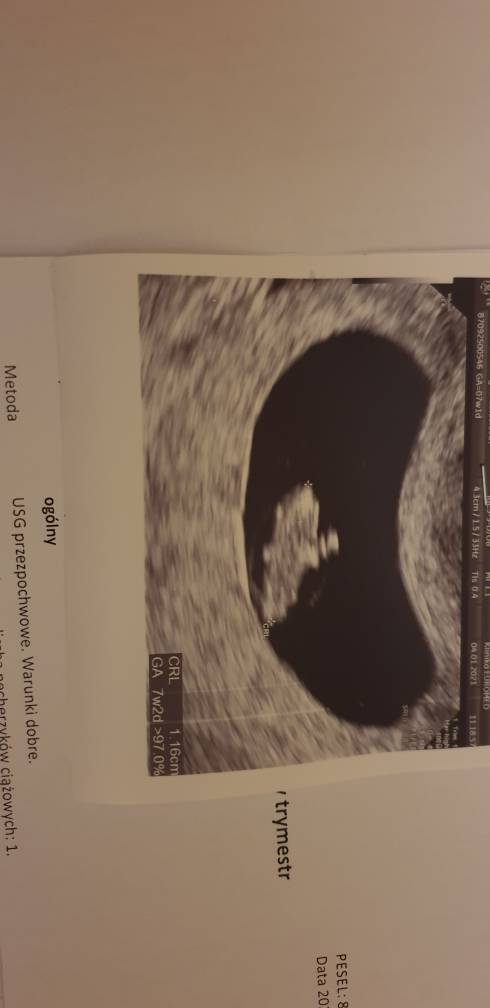

Ja już jestem po wizycie u swojej gin. Wszystko jest w porządku, maluch rośnie dziś mierzył 1,16 mm jest to 7+1 termin z OM idealnie pokrywa się z tym z usg termin porodu wyznaczony na 22.08. Kolejna wizyta dopiero 15.02 od razu będę miała usg prenatalne. A co do plamień to ustały i przyczyny nie widać, dalej mam brać luteinę do 13 tyg ciąży zapobiegawczo. Moja gin mówiła, że czasami taka uroda i plamienia się zdarzają i nie muszą oznaczać nic złego.

Ja już jestem po wizycie u swojej gin. Wszystko jest w porządku, maluch rośnie dziś mierzył 1,16 mm jest to 7+1 termin z OM idealnie pokrywa się z tym z usg termin porodu wyznaczony na 22.08. Kolejna wizyta dopiero 15.02 od razu będę miała usg prenatalne. A co do plamień to ustały i przyczyny nie widać, dalej mam brać luteinę do 13 tyg ciąży zapobiegawczo. Moja gin mówiła, że czasami taka uroda i plamienia się zdarzają i nie muszą oznaczać nic złego.Zobacz załącznik 1222649